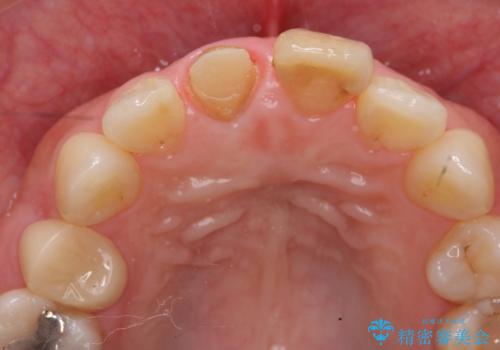

- 歯の神経を除去したのちの、変色の改善を希望され来院されました。

再度根管治療を行ったのちの、オールセラミッククラン治療を計画します。

天然歯を再現したリアルな仕上がりに満足いただくことができました。

オールセラミッククラウン スペシャルプランは細やかな色調の再現に優れ、目立つ前歯の審美的な仕上がりがより達成されやすいプランです。